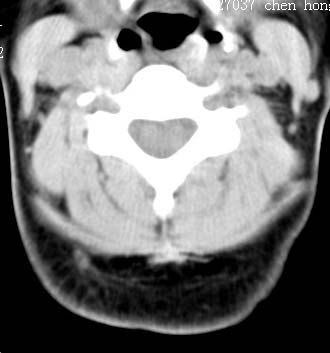

以下是引用sos.la在2008-6-24 5:29:00的发言:[br]可疑项部皮下脂肪肉瘤.穿刺活检.

以下是引用pujunzhi在2008-6-24 7:29:00的发言:[br]后颈部脂肪瘤

以下是引用随光逐影在2008-6-24 7:46:00的发言:[br]考虑项部皮下脂肪瘤或脂肪沉积。